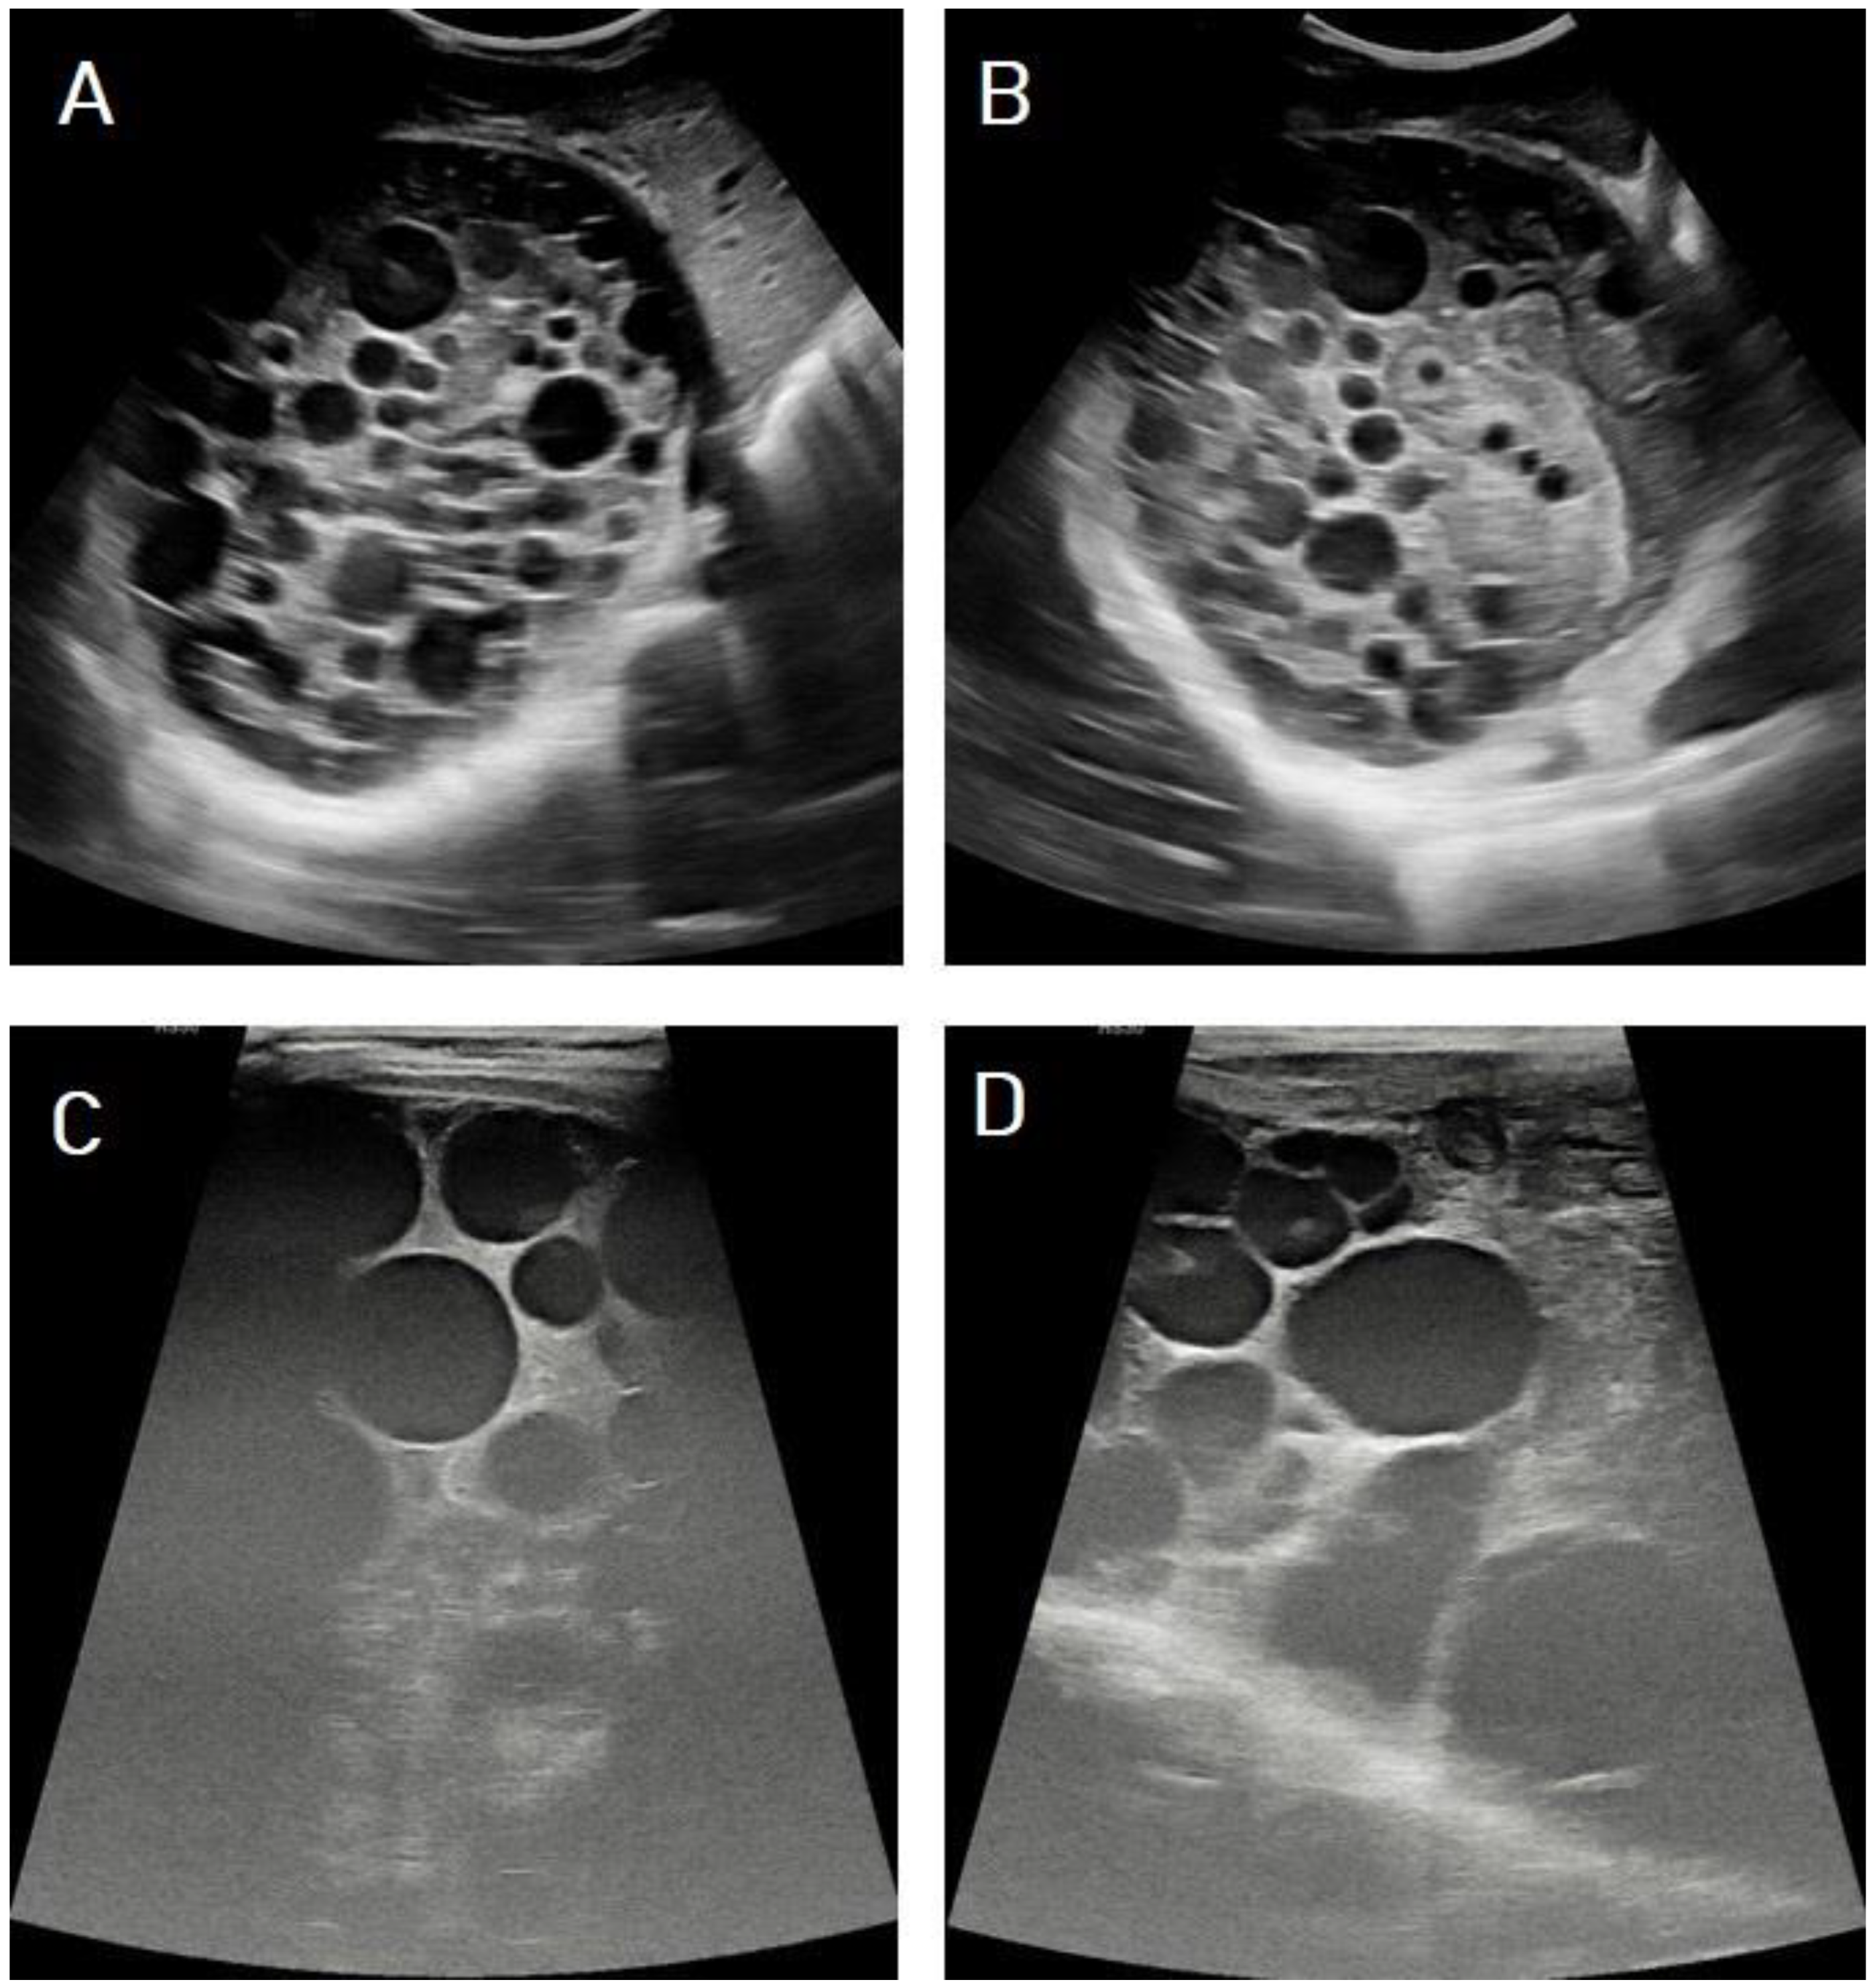

5.1. Hydatid Cysts of the Liver